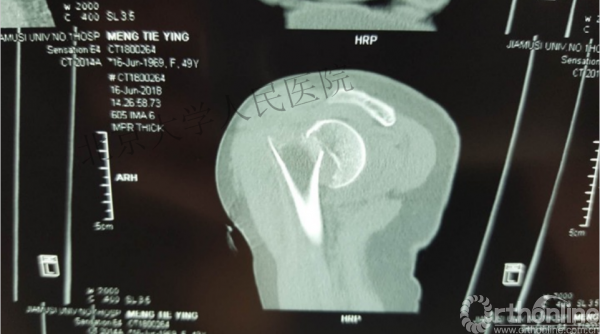

内侧皮质粉碎,低位外科颈骨折,肱骨头-干角维持困难。

术后复位丢失,肱骨头内翻畸形。

能否该偏心固定(钢板)为髓内固定,增加力臂?

此时对比髓内钉是不是有很大优势?